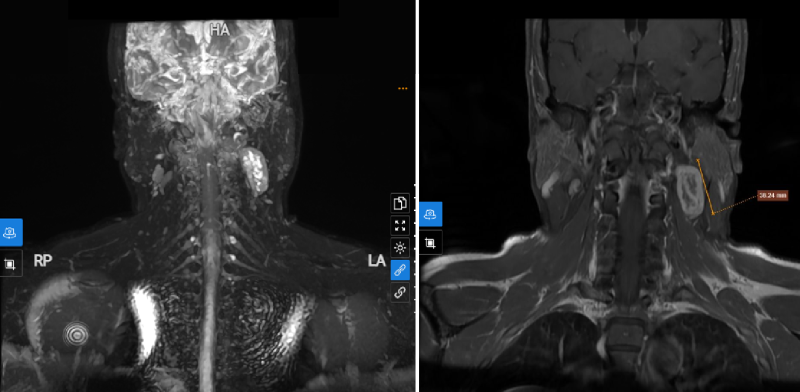

Phòng khám Đa khoa MEDLATEC Tây Hồ mới tiếp nhận một nữ bệnh nhân đến khám với tình trạng đau vùng cổ gáy kèm tê bì tay trái. Tưởng rằng chỉ là dấu hiệu của...